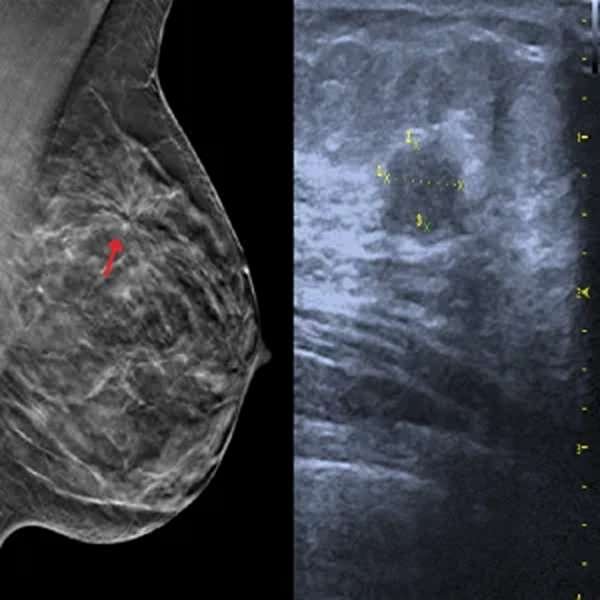

Ecografía de mamas

La ecografía de mamas es un estudio por ultrasonido que permite evaluar el tejido mamario en detalle, detectando quistes, nódulos, tumores o alteraciones en las glándulas mamarias. Se utiliza como complemento de la mamografía, especialmente en mujeres jóvenes con tejido mamario denso, y es clave en el diagnóstico de enfermedades benignas o cancerígenas. Es un procedimiento seguro, indoloro y no invasivo, ideal para el control preventivo y el seguimiento de anomalías detectadas en exámenes previos.